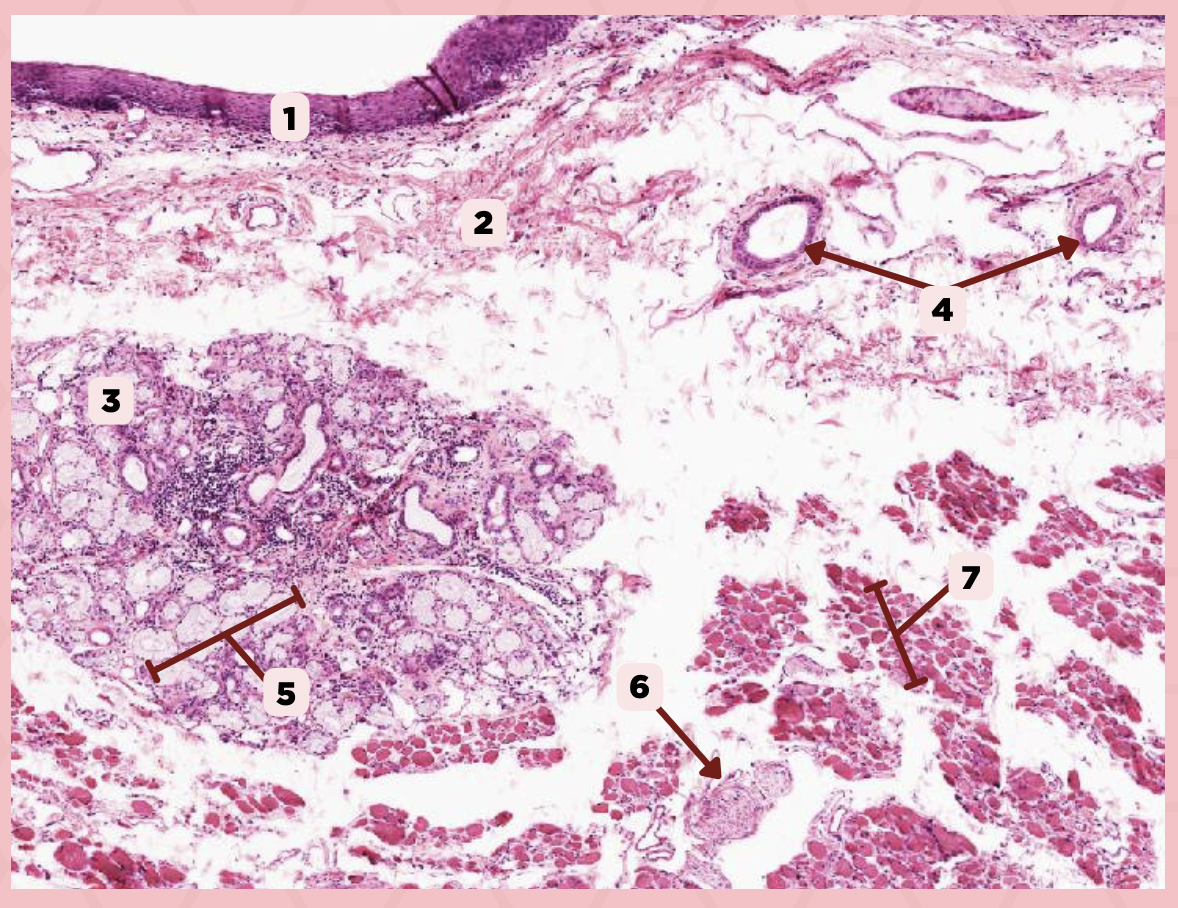

Lip

What is the specimen showed in the picture?

Epidermis

Identify the structure labeled as 1.

Dermis

Identify the structure labeled as 2.

Arrector Pilli Muscle

Identify the structure labeled as 3.

Hair Follicle

Identify the structure labeled as 4.

Sebaceous Glands

Identify the structure labeled as 5.

Lip

What specimen is showed in the picture?

Labial Glands (in the Mucosa)

Identify the structure labeled as 1.

Skeletal Muscle Cells

Identify the structure labeled as 2.

Lamina Propria

Identify the structure labeled as 3.

Mucosa

Identify the structure labeled as 4.

Lip

What specimen is showed in the picture?

Skeletal Muscle Fibers

Identify the structure labeled as 1.

Labial Glands

Identify the structure labeled as 2.

Cheek

Identify the specimen.

Mucosa

Identify the structure labeled as 1.

Lamina Propria

Identify the structure labeled as 2.

MALT

Identify the structure labeled as 3.

Blood Vessels

Identify the structure labeled as 4.

Buccal Glands

Identify the structure labeled as 5.

Nerve

Identify the structure labeled as 6.

Muscle Fascicles

Identify the structure labeled as 7.